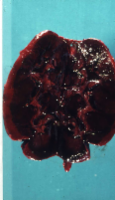

Die Abbildung 10 zeigt den Gefäßabbruch der Art. hypogastrica links bei Abstosungsreaktion der implantierten Niere und die Abbildung 11 das explantierte Organ